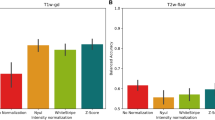

Comparative analysis of the radiomics features on T2FLAIR before and after RT

Under different dose gradients of this sequence, there were 0, 5, 2, 1, 0, 1, and 0 radiomics features with statistically significant differences before and after RT. These numbers were significantly less than T1 and T1+C sequences, and there were no statistically significant differences in the dose gradients of 0–5 Gy (low-dose) and > 40 Gy (high-dose). Among these features, GLSZM-LargeAreaHighGrayLevelEmphasis under dose gradients of 5–10 Gy and 10–15 Gy was a general feature, with change rates of − 3.08% and − 10.87%, respectively; the change showed an upward trend with increasing dose.